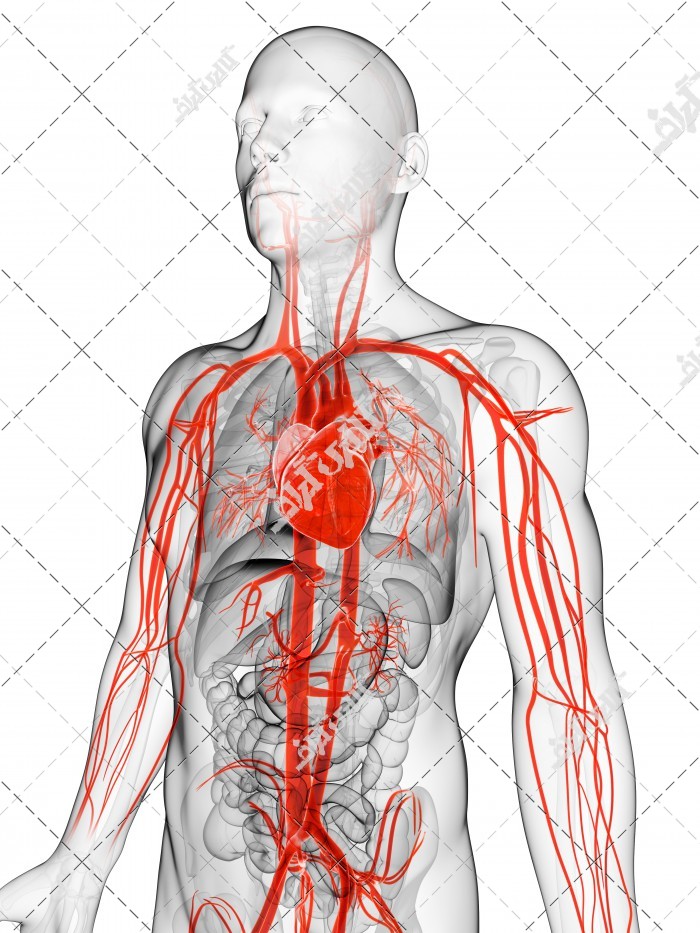

عکس اسکلت بدن انسان با کیفیت. عکس اسکلت عکس اسکلت برای پروفایل عکس اسکلت انسان عکس اسکلت خفن عکس اسکلت بدن انسان با کیفیت عکس اسکلت بدن انسان عکس اسکلت ترسناک عکس اسکلت فانتزی عکس اسکلت فانتزی دخترانه پرچم عکس اسکلت. عکس با کیفیت اسکلت داخلی انسان و درد و گرفتگی در ناحیه استخوان زانو ویژه استفاده در امور تبلیغاتی و تجاری طراحی کاتالوگ بروشور و تراکت با موضوع پزشکی فیزیوتراپی ارتوپد دکتر روماتیسم فیریوتراپ طب فیزیکی. عکس اسکلت بدن انسان زن و مرد آناتومی ساتین 16 سپتامبر 2017. اسکلت داربست بدن است تمام قسمت های بدن روی اسکلت قرارگرفته اند بدن انسان از ۲۰۶ قطعه استخوان تشکیل شده است این استخوان ها طوری با نظم کنار هم قرار گرفته اند که انسان را قادر می سازد حرکات دقیقی داشته باشد.

اسکلت جمجمه و گردن انسان ستون فقرات آناتومی اسکلت جمجمه و گردن انسان ستون فقرات آناتومی تصویر با کیفیت را از لینک زیر می توانید دانلود کنید. ۱ مطلب با کلمه ی کلیدی عکس اسکلت بدن انسان با کیفیت ثبت شده است گالری نسیم جدید ترین و با کیفیت ترین عکس های مناسبتی. عکس با کیفیت آناتومی اسکلت بدن انسان و درد و دیسک در قسمت مهره های ستون فقرات کمر ویژه استفاده در امور تبلیغاتی و تجاری طراحی کاتالوگ بروشور و تراکت با موضوع بیمارستان ها و کلینیک ها و درمانگاه ها و مطب ها پزشکان و.